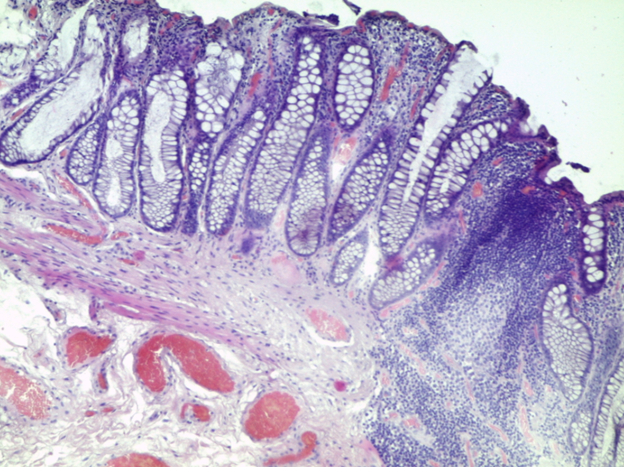

Препарат № 381

АДЕНОКАРЦИНОМА В ВОРСИНЧАТОЙ АДЕНОМЕ ТОЛСТОЙ КИШКИ

Окраска: гематоксилин-эозин

Полиповидное опухолевое образование толстого кишечника из пролиферирующего железистого эпителия с признаками дисплазии, покрывающего ворсинчатые выросты – аденома. В опухоли определяются очаги инвазивной внутрислизистой аденокарциномы в виде плохо сформированных сливающихся железистых комплексов из атипичного эпителия. В крае препарата сохранена нормальная слизистая толстой кишки.

Отметить:

1. Ворсинчатая аденома

2. Аденокарцинома

3. Нормальная слизистая.